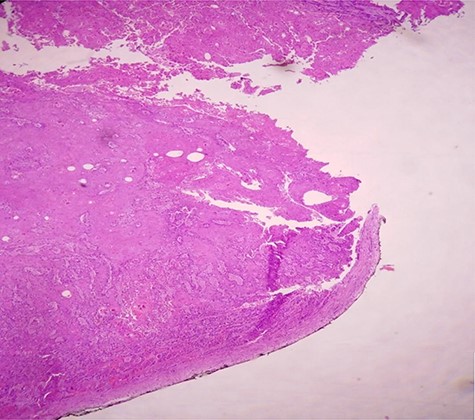

H & E staining viewed under x10 with Olympus CX23 showing bladder wall infiltration with a SCC perforating serosa (bladder surface inked).